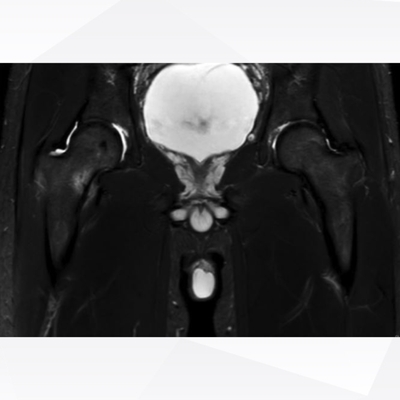

Click on an image below to view more info.